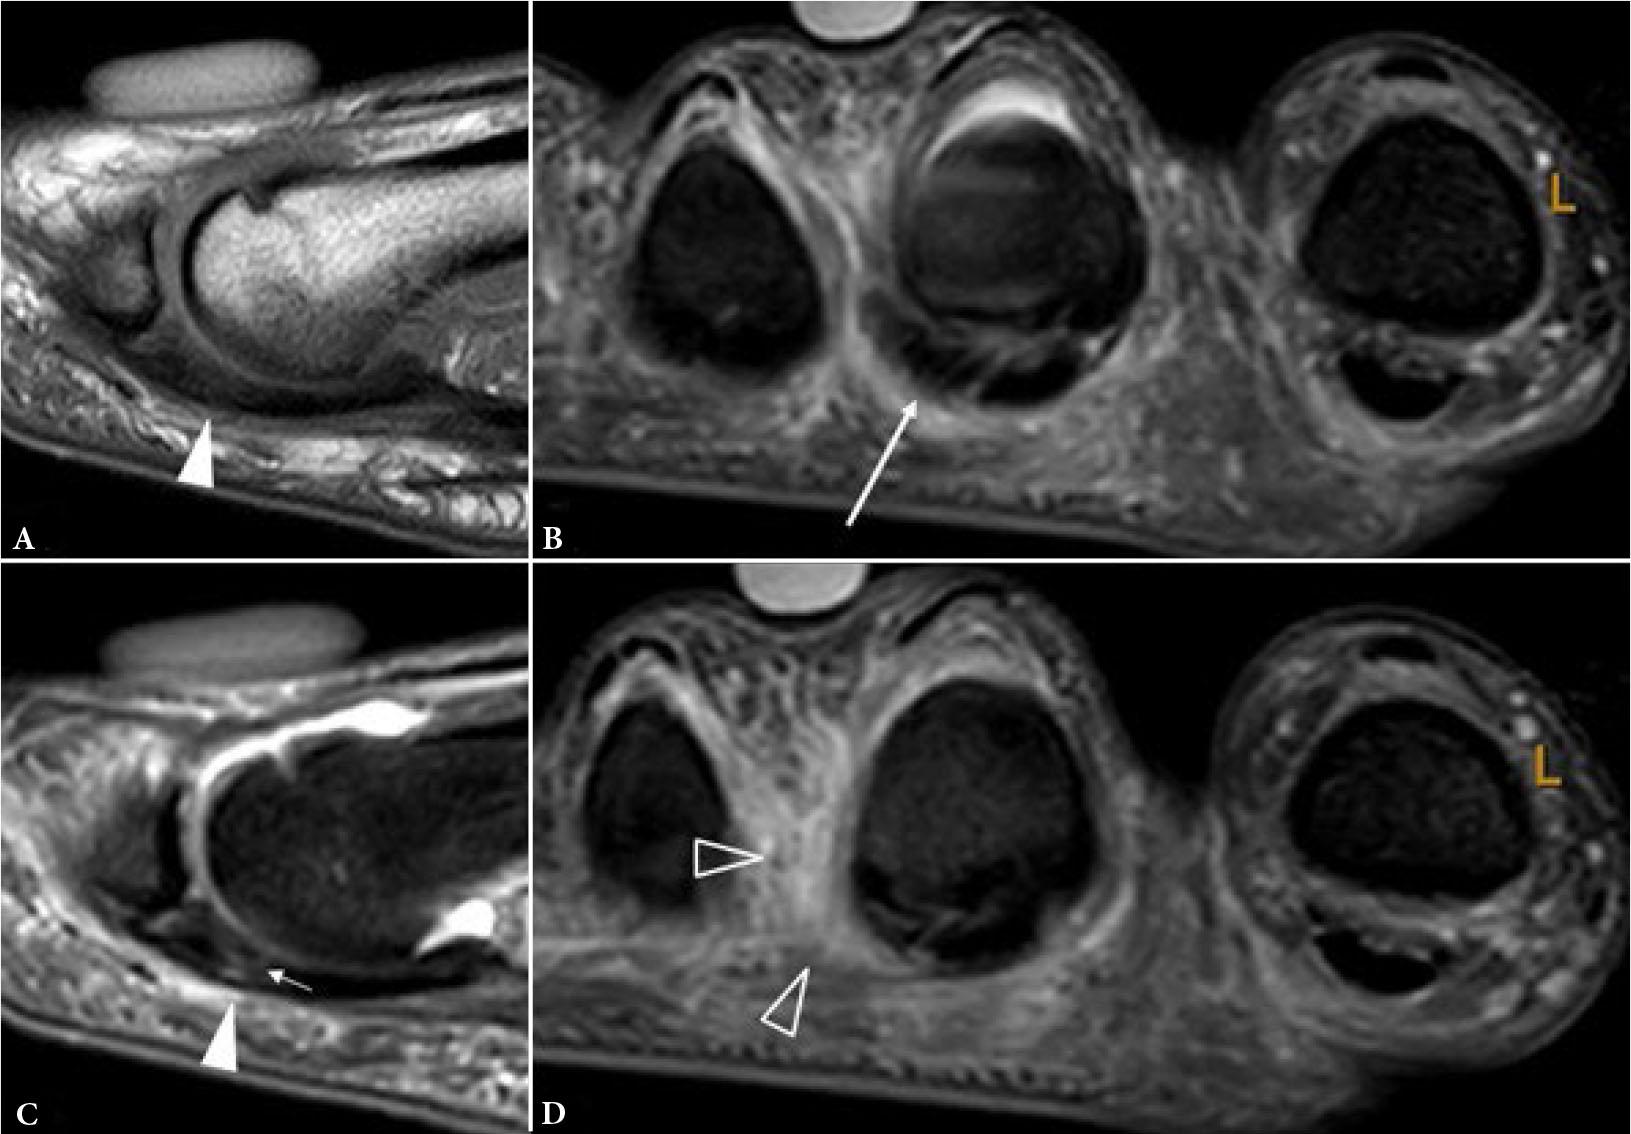

Even more so than the 1st MTP joint, the plantar plates of the lesser MTP joints resist joint hyperextension and provide sagittal stability(11). Distally, the plantar plates are firmly attached to the proximal phalangeal bases while proximally, they are loosely attached to the metacarpal necks by fibro-synovial tissue(12). On either side, the plantar plates are firmly attached to the medial and lateral accessory collateral ligaments (Fig. 13) and, as such, co-existent injury of the plantar plate and accessory ligaments commonly occurs(12). Plantar plate tear can lead to MTP joint medial or lateral deviation, dorsal subluxation, and hammer toe(13). The normal plantar plate and plate tears are shown on US and MRI in Fig. 14 and Fig. 15. As with the 1st MTP joint, a midline hyperintense zone, measuring up to 2.5 mm long, at the phalangeal base is a normal anatomic recess(11) (Fig. 10). This is less frequently appreciated on US as a hyperechoic zone.

Fig. 14.

31–year-old female professional basketball player with forefoot pain. A, B. Consecutive longitudinal greyscale US images shows moderately thickened plantar plate (arrowheads) of the 2nd MTP joint with a long intrasubstance tear (short arrows). C. Transverse greyscale US image shows moderate pericapsular fibrosis (long arrow) inferolateral to the 2nd MTP joint. D. Longitudinal greyscale US image of the asymptomatic normal contralateral 2nd MTP joint plantar plate for comparison. (images courtesy of Dr James Linklater)

Fig. 15.

Same patient as previous figure. Sagittal A. proton density (PD) and B. T2W FS images shows a moderately thickened plantar plate (arrowheads) of 2nd MTP joint with intrasubstance tear (short arrow). C, D. Coronal T2W fat-suppressed MR images shows moderate-severity reactive pericapsular fibrosis (long arrow) inferolateral to the 2nd MTP joint with moderate pericapsular inflammation (open arrowheads). The plantar plate tear was confirmed and treated surgically, with subsequent return to sports (images courtesy of Dr James Linklater)

The 2nd, followed by the 3rd, MTP joint plantar plates are the most frequently injured(12). Plantar plate tears typically occur at the junction between the plantar plate and the accessory collateral ligament close to the phalangeal attachment, most commonly at the inferolateral aspect of the joint (Fig. 13). On US, most plantar plate tears are seen as discrete partial or full thickness hypoechoic defects in the plate substance(13,14). Flattening or attenuation may occur with plantar plate degeneration. When the plantar plate is completely torn, the flexor digitorum tendon may directly contact the metatarsal head(13,14). In the chronic setting, reactive pericapsular fibrosis can be seen as a non-compressible hypoechoic cuff of tissue abutting the plantar and inferolateral (or inferomedial) aspects of the MTP joint(13,14). US should be performed in both longitudinal and transverse planes, scanning the plantar aspect of the MTP joint slowly from lateral to medial and from distal to proximal, with angling of the transducer to avoid anisotropy. Most injuries occur at the distal attachment of the plate. Longitudinal US is best to detect and characterize tears while transverse US is useful to delineate the eccentric location of pericapsular fibrosis and to exclude subluxation of the flexor digitorum tendon. Longitudinal US during toe dorsiflexion can improve tear detection and appreciation of MTP joint subluxation(14).

For MR imaging, T1-weighted (T1W) coronal images are usually the most helpful as routine sagittal forefoot images do not always image the plantar plate in a true sagittal plane(12) (Fig. 15). Performing MRI in the prone position, with the foot in plantarflexion, results in less magic angle artifact and less movement artefact potentially facilitating assessment of the plantar plate(11). Prone positioning also leads to slight plantar shift of the interdigital soft tissues improving assessment of Morton’s neuroma(15). Dynamic US assessment during MTP joint dorsiflexion or during dorsal drawer (Lachman) testing can help assessment of plantar plate integrity and MTP joint stability. Compared with surgical findings, the pooled sensitivity (93%) of US for detecting plantar plate tears is comparable to that of MRI (89–95%), though MRI has a higher specificity (54–83%) than US (33–52%)(16). A negative US examination makes plantar plate injury very unlikely. If US is positive or equivocal, MRI can provide more specificity as to the nature of the injury and yield a more global assessment of the MTP joint(17).